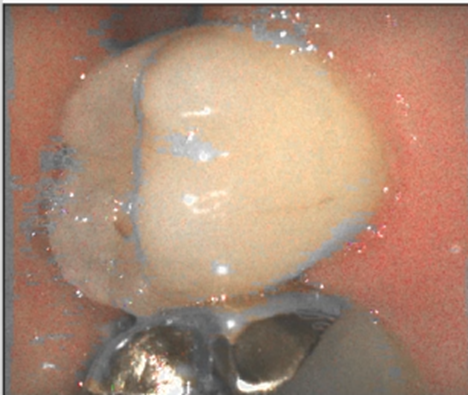

구강 스캔 전 환자의 구강 상태를 확인해야 합니다. 구강 내에 혈액/타액이 과도하게 있는 경우 스캔 데이터에 영향을 줄 수 있으므로 스캔 전 반드시 혈액과 타액을 제거해야 합니다.

구강 스캐너는 구강 상태를 있는 그대로 획득하여 데이터를 생성하기 때문에, 치은 연하 마진 또는 불분명한 마진 케이스의 경우 정확한 마진 데이터 획득을 위해 치은 격리가 필요합니다.

치은 격리 방법은 레이저를 이용한 치은 절개, 치은 압배사를 사용한 격리 등이 있습니다.

| 올바르지 않은 구강 환경 | 올바른 구강 환경 |